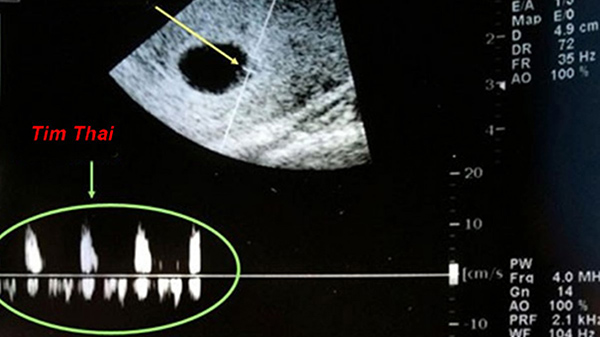

Thời kì mang thai của mẹ sẽ kéo dài 9 tháng 10 ngày, tức là vào khoảng 40 tuần. Theo ý kiến của các bác sĩ chuyên khoa thì vào tuần thứ 6 đến thứ 7 của thai kì thì mẹ có thể nghe thấy tim thai qua dụng cụ chuyên dụng của bệnh viện.

Tim thai được đánh giá là bộ phận được hình thành sớm nhất, chỉ trong vòng tuần các cấu trúc như ống tim, vách ngăn đã dần xuất hiện. Để phát hiện các mạch lớn và dòng máu chuyển động theo nhịp đập của tim thai bác sĩ sẽ tiến hành siêu âm Doppler.